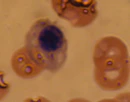

Нормобласт проходит четыре стадии своего развития.

| Схематическое изображение | Описание | Вид в микроскопии мазка |

| Проэритробласт (пронормобласт, препрорубрицит) | Нет | |

| Базофильный нормобласт (прорубрицит) | ||

| Полихроматофильный нормобласт (полихроматический нормобласт, рубрицит) | ||

| Ортохроматофильный нормобласт (ортохроматический нормобласт, метарубрицит) |